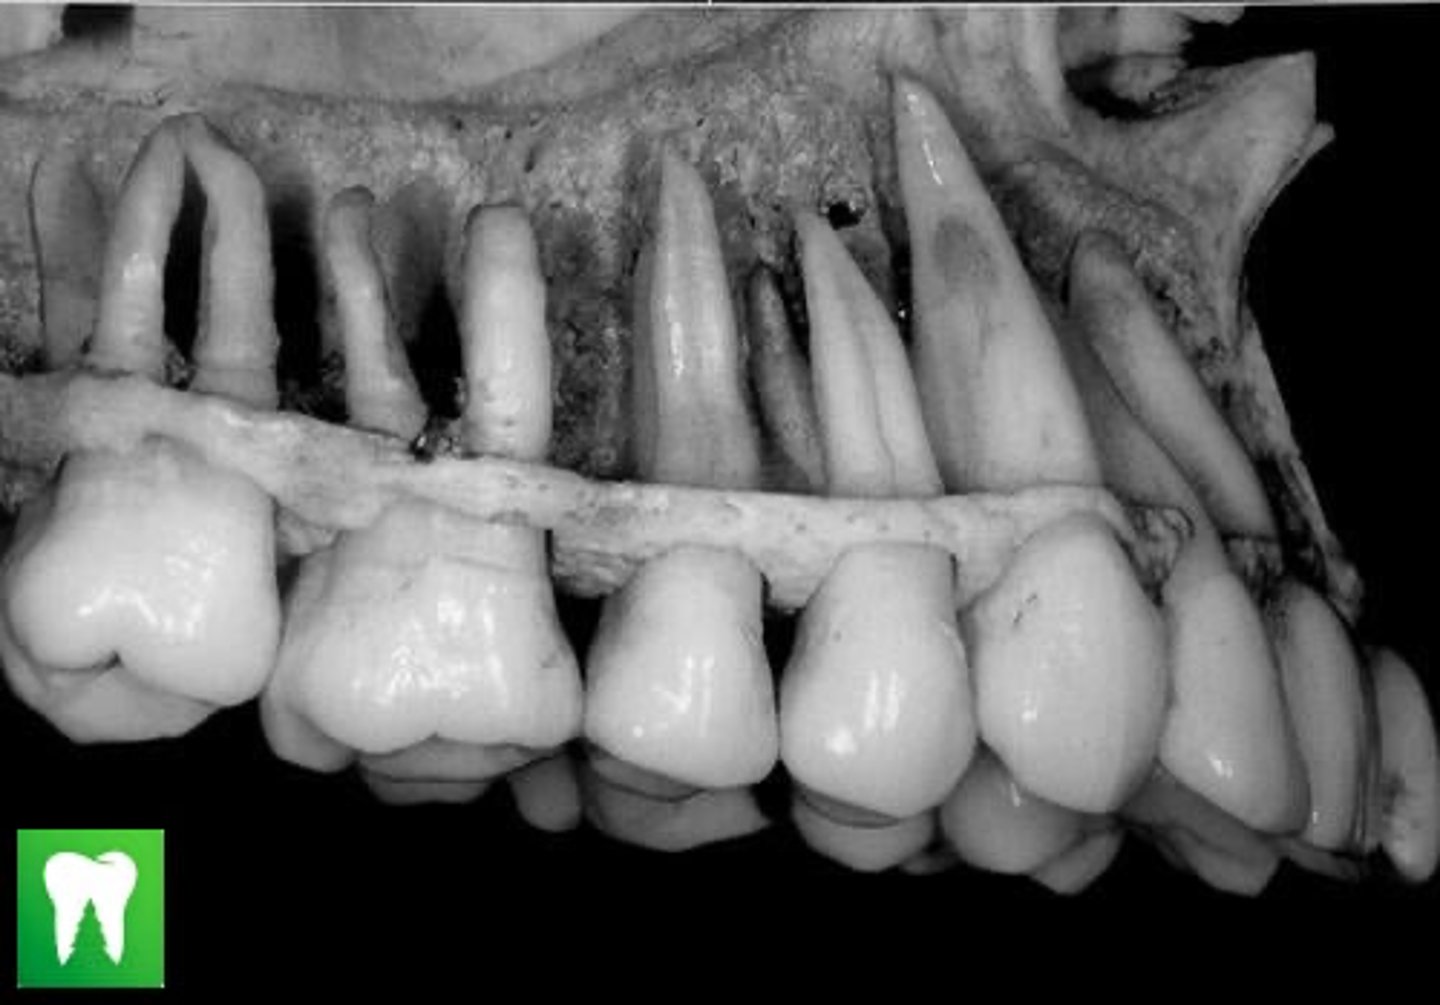

REVIEW DENTAL ANATOMY BASICS:

- Slides 116-120

4

Anterior teeth are composed of ____ Lobes

- named mesiolabial, middle labial, and distolabial lobes.

Canine

Longest and strongest root in both arches

Maxillary 1st Premolar

Anterior teeth and premolars normally have single roots.

An EXCEPTION is the ____ ____ ____ which normally has 2 roots: B & L root branches

Mandibular 2nd Premolar

Most Premolars have ____ lobes.

Named: mesiobuccal, middle buccal, distobuccal, and lingual lobes.

The EXCEPTION is the ____ ___ ____ bc it has TWO lingual cusps= 5 lobes

True

T/F: Unlike the anterior teeth and premolars, molars do not exhibit facial developmental depressions. Evidence of lobe separation can be found in the central groove, which divides buccal from lingual lobes. The two lingual lobes are separated by the distolingual groove, and the two buccal lobes are divided by the buccal groove.

3

2

Max molars have ___ roots

Mand molars have ____ roots